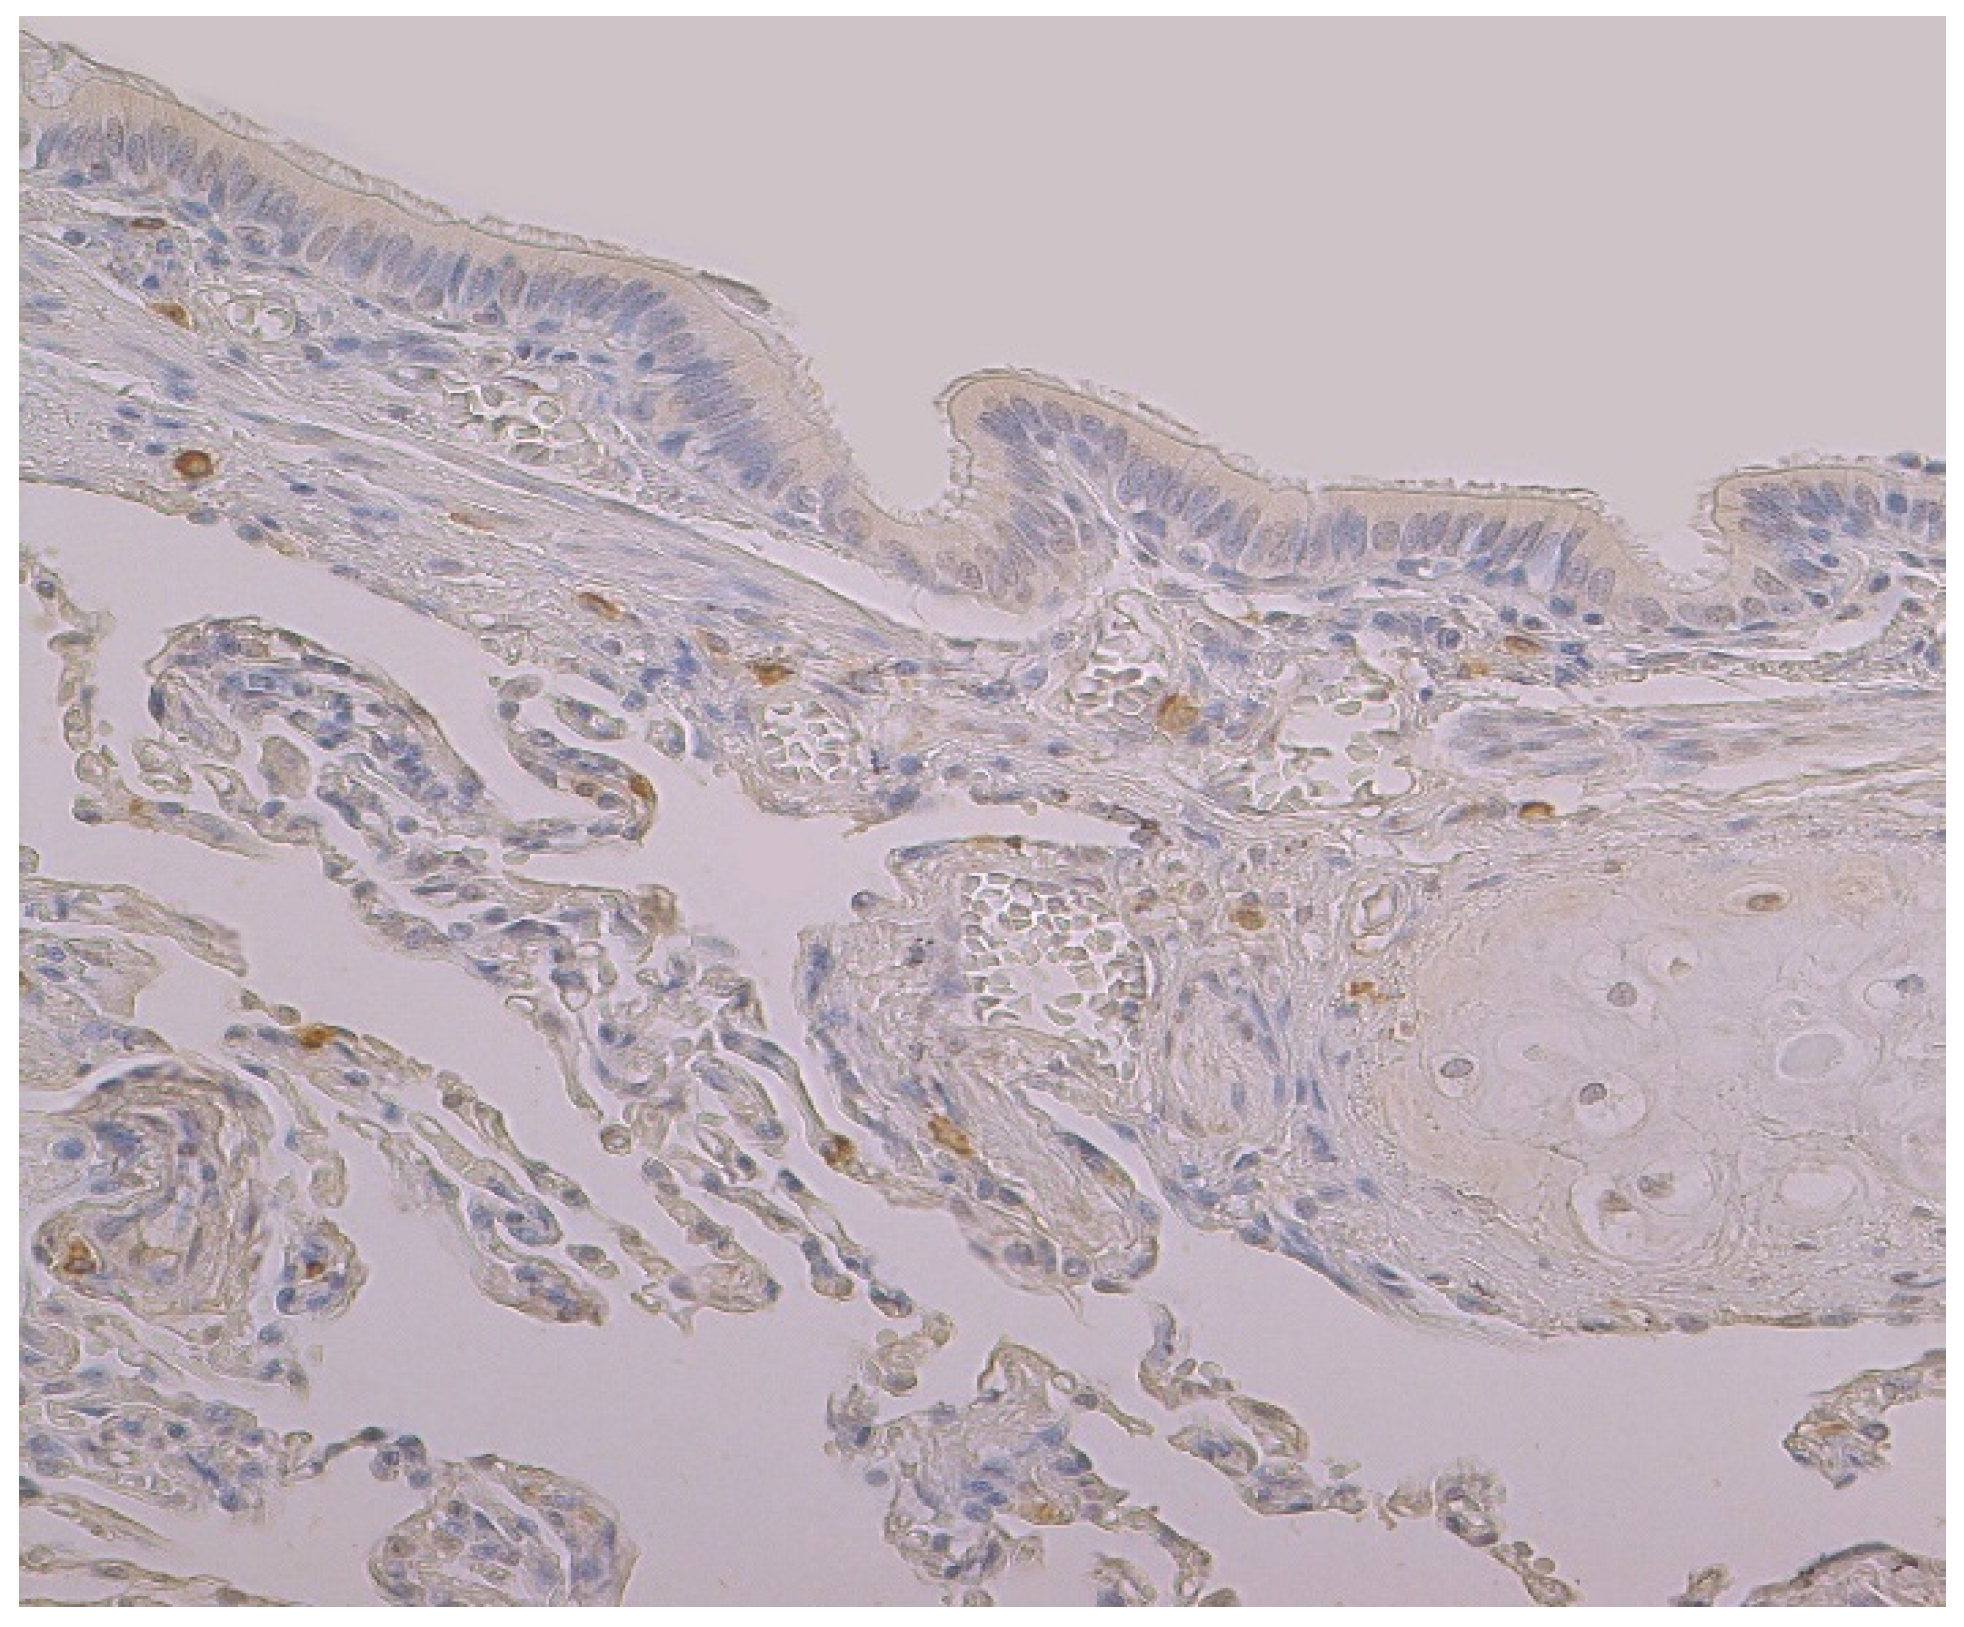

3.1. Tissue Review

3.2. Immunohistochemical (IMH) Data